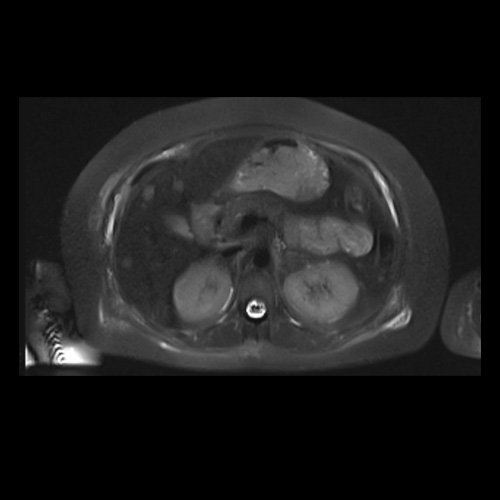

RMN de abdomen con contraste endovenoso (14/02/26)  Corte axial (T2): múltiples lesiones sólidas de distribución difusa, levemente hiperintensas.

• RMI abdomen y pelvis con contraste EV (14/02/26): En las bases pulmonares se visualizan atelectasias laminares bibalsales. No se identifica derrame pleural. El hígado es de forma, tamaño y situación normal. La superficie es lisa, los bordes son agudos. Se observan múltiples lesiones sólidas de distribución difusa, levemente hiperintensas en T2, con restricción en difusión y realce homogéneo tras la administración de contraste EV, la de mayor tamaño de 15 mm en segmento VII. Sugiero conocimiento histológico. La vía biliar intra y extrahepática es de calibre conservado. La vesícula biliar es de forma y situación habitual, sus paredes son finas y no presenta imágenes hipointensas en su interior, que sugieran la presencia de litiasis. El bazo es de forma, tamaño y situación normal, sin efectos de masa focales. El páncreas es de forma, tamaño y situación normal, sin efectos de masa. El Wirsung es de calibre conservado. Glándulas adrenales de forma, tamaño y situación normal, sin efectos de masa. Ambos riñones son de forma, tamaño y situación normal, con adecuada diferenciación córtico subcortical. No se observan alteraciones a nivel de la vía excretora. No se observan adenomegalias retroperitoneales ni intraperitoneales. La aorta abdominal, las arterias iliacas primițivas, internas, externas y femorales son de trayecto y calibre normal La vena cava inferior, las venas ilíacas primitivas, internas, externas y femorales son de trayecto y calibre normal. No impresionan alteraciones a nivel del tracto gastrointestinal. La vejiga es de paredes finas, normalmente distensibles, sin evidencia de lesiones endoluminales ni parietales. Mioma transmural en hoja anterior de útero que mide 55 x 47 mm sin signos de complicaciones. Imagen ovalada de contenido líquido que mide 65 x 52 mm en el espesor del tejido celular subcutáneo de región antero-superior de muslo derecho, por delante de músculo sartorio, que no presenta realce tras la administración de contraste EV.